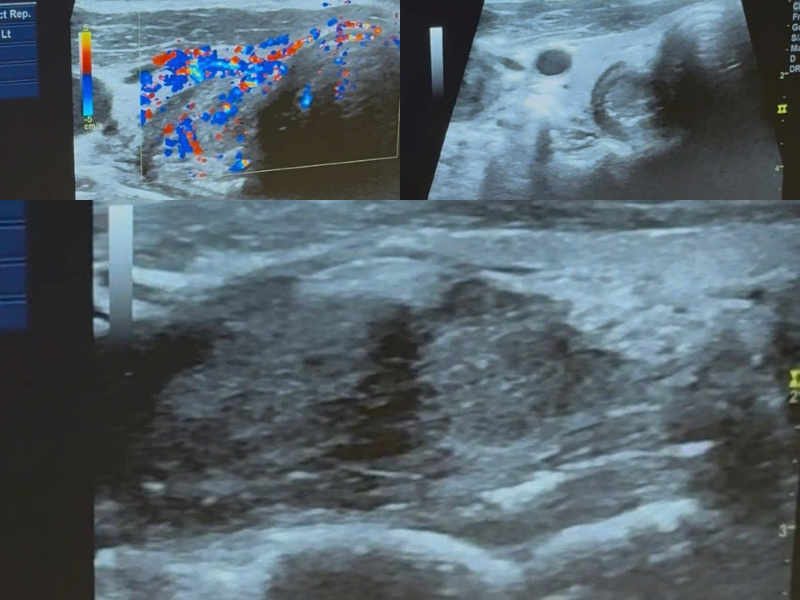

Hình ảnh siêu âm gợi ý ung thư hạ hầu

Siêu âm ghi nhận:

• Khối đặc giảm âm kích thước 27×22mm

• Giới hạn kém rõ

• Xâm nhiễm miệng thực quản

• Tăng sinh mạch máu trên Doppler

• Hạch cổ hai bên mất rốn mỡ, hoại tử trung tâm

Khối u vùng hạ hầu

Hạch di căn

Kết luận siêu âm

Theo dõi K hạ hầu lệch phải, xâm nhiễm miệng thực quản, di căn hạch cổ hai bên.

Điểm đáng chú ý: thực quản bị kéo lệch phải so với khí quản – dấu hiệu xâm lấn ngoài thành.